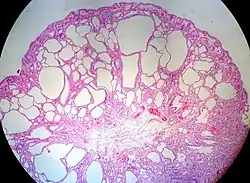

Juvenile Polyp | Upper GI tract and colon | Cystically dilated glands with expanded lamina propria | Not inherently, may develop dysplasia | ![]() |

Juvenile polyposis syndrome, identical polyps in Cronkhite–Canada syndrome |